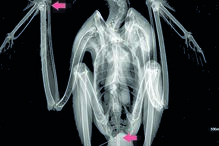

Ave foi atingida por vários projéteis. Foi encontrada por um popular.

No exame radiológico "foram encontrados dois projéteis de caçadeira no pulso direito e na cauda, mas também uma fissura no cúbito direito, que apresentava ainda restos de munição", esclareceu a mesma fonte.